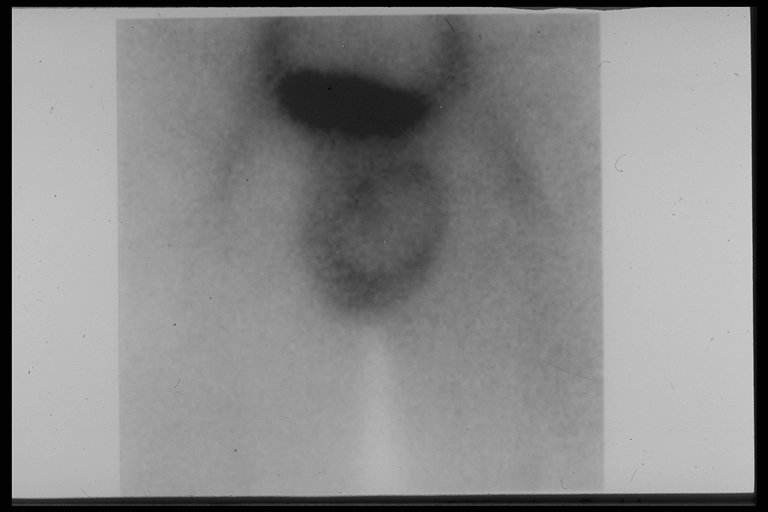

Testicular scan is the best investigation to confirm the testicular torsion, No uptake of radionuclide at the testicular core but increased uptake around the testis

" Halo sign " with increased uptake of radionuclide around the testis but no uptake at the core suggests that the vascular supply is interrupted in a case with right testicular torsion